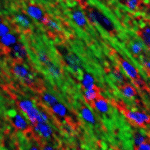

靶向型脂质递送系统

模块化脂质共组装策略实现靶向核酸递送及重大疾病治疗机制创新:提出“模块化分子组装”策略,设计具备靶向功能的脂质模块, 组装构建可高效定向递送至肝星状细胞、巨噬细胞、小胶质细胞等细胞的核酸载体;首次提出“正反馈增效”靶向递送机制,并在心脑血管、肝代谢等疾病动物模型中展现出显著的治疗效果,为重大疾病治疗开辟新路径。

代表性论文:Nature Communications. 2023; ACS Nano,2024; ACS Nano,2024; ACS Nano,2023; ACS Nano,2023